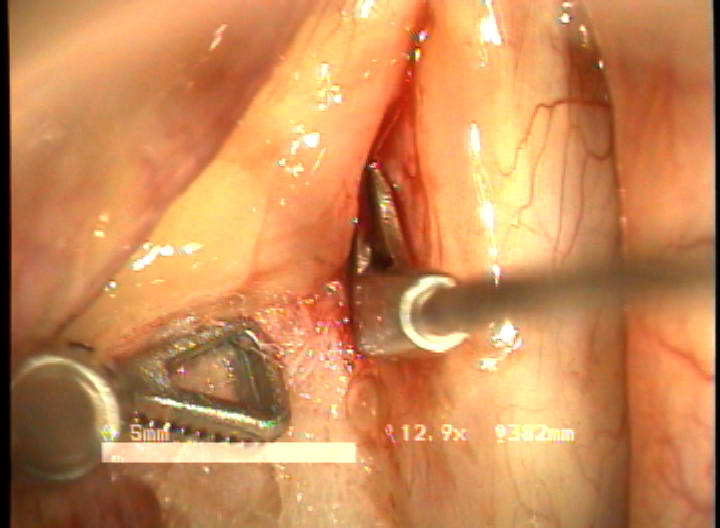

방법 : 2006년 1월 부터 2007년 12월 까지 예송이비인후과에서 전성문횡격막으로 진단되어 double rotational microflap laryngoplasty를 시행받고 1년간 장기추적이 가능하였던 6명의 환자를 대상으로 후향적 분석을 시행하였다. 원인적인 요인과 동반질환으로는 후두유두종 술후 합병증 4례, 후두외상 1례, 폴립양성대 1례 였다. 남녀 각각 3례였으며, 평균연령은 39세 였다. 추적기간은 21.5 개월이었다. 술 후 2개월과 6개월에 음성개선에 대한 주관적인 음성평가를 시행하였으며, 음성분석검사와 후두스트로보스코피 검사를 통하여 객관적인 음성평가와 성대점막파동의 변화를 관찰하였다. 통계적 유의성은 Wilcoxon Signed Ranks Test로 검정하였다.

결과 : 음성개선에 대한 주관적인 평가로서 수술전 Voice Handicap Index는 평균 19.7 에서 술후 11.5로 감소하였다. 공기역학적인검사상 성문하압은 5.5에서 4.5로 감소되었으며, 최대발성시간 13.7에서 16.1로 증가되었다. 음성분석검사상 sPPQ, sAPQ, NHR, SPI, DSH가 모두 통계학적으로 유의하게 감소하였다. 후두스토로보스코피검사상 모든 례에서 재발의 징후없이 성대점막파동의 의미있는 호전이 나타났다. 합병증으로 1례에서 염증성 육아종형성이 관찰되었으나 미세피판의 괴사나 탈락은 관찰되지 않았다.

결론 : 전성문횡격막의 새로운 수술방법으로서 double rotational microflap laryngoplasty는 일차수술로 만족스러운 음성학적 치료결과를 얻을 수 있는 매우 유용한 술식이라 사료된다.